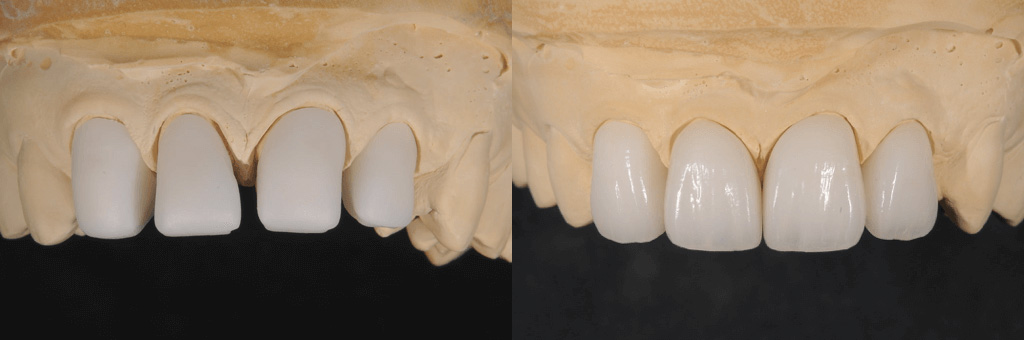

図4

被せ物を装着する前と装着した後。天然の歯に近い形で再現できています。